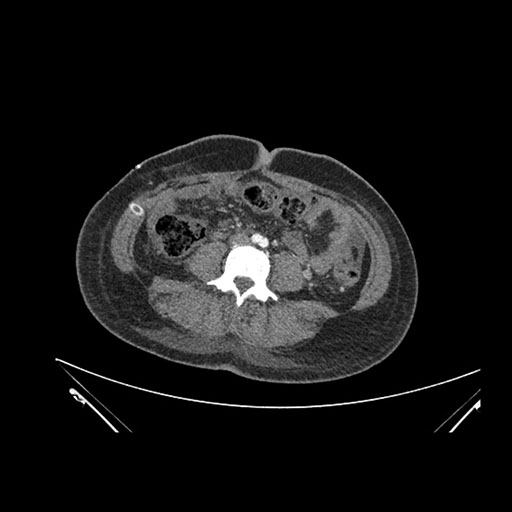

Imaging Analysis

Look through the patient's CT scan to identify any areas of concern for the necessary procedure.

Coronal Venous

Based on initial findings, which issue(s) would you be most concerned about?